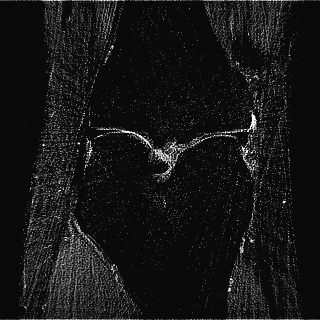

This article presents a novel undersampled magnetic resonance imaging (MRI) technique that leverages the concept of Neural Radiance Field (NeRF). With radial undersampling, the corresponding imaging problem can be reformulated into an image modeling task from sparse-view rendered data; therefore, a high dimensional MR image is obtainable from undersampled $k$-space data by taking advantage of implicit neural representation. A multi-layer perceptron, which is designed to output an image intensity from a spatial coordinate, learns the MR physics-driven rendering relation between given measurement data and desired image. Effective undersampling strategies for high-quality neural representation are investigated. The proposed method serves two benefits: (i) The learning is based fully on single undersampled $k$-space data, not a bunch of measured data and target image sets. It can be used potentially for diagnostic MR imaging, such as fetal MRI, where data acquisition is relatively rare or limited against diversity of clinical images while undersampled reconstruction is highly demanded. (ii) A reconstructed MR image is a scan-specific representation highly adaptive to the given $k$-space measurement. Numerous experiments validate the feasibility and capability of the proposed approach.